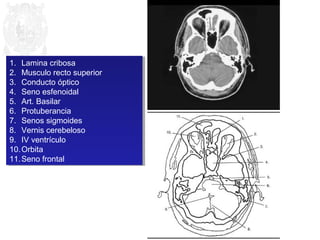

1. Lamina cribosa

2. Musculo recto superior

3. Conducto óptico

4. Seno esfenoidal

5. Art. Basilar

6. Protuberancia

7. Senos sigmoides

8. Vernis cerebeloso

9. IV ventrículo

10.Orbita

11.Seno frontal